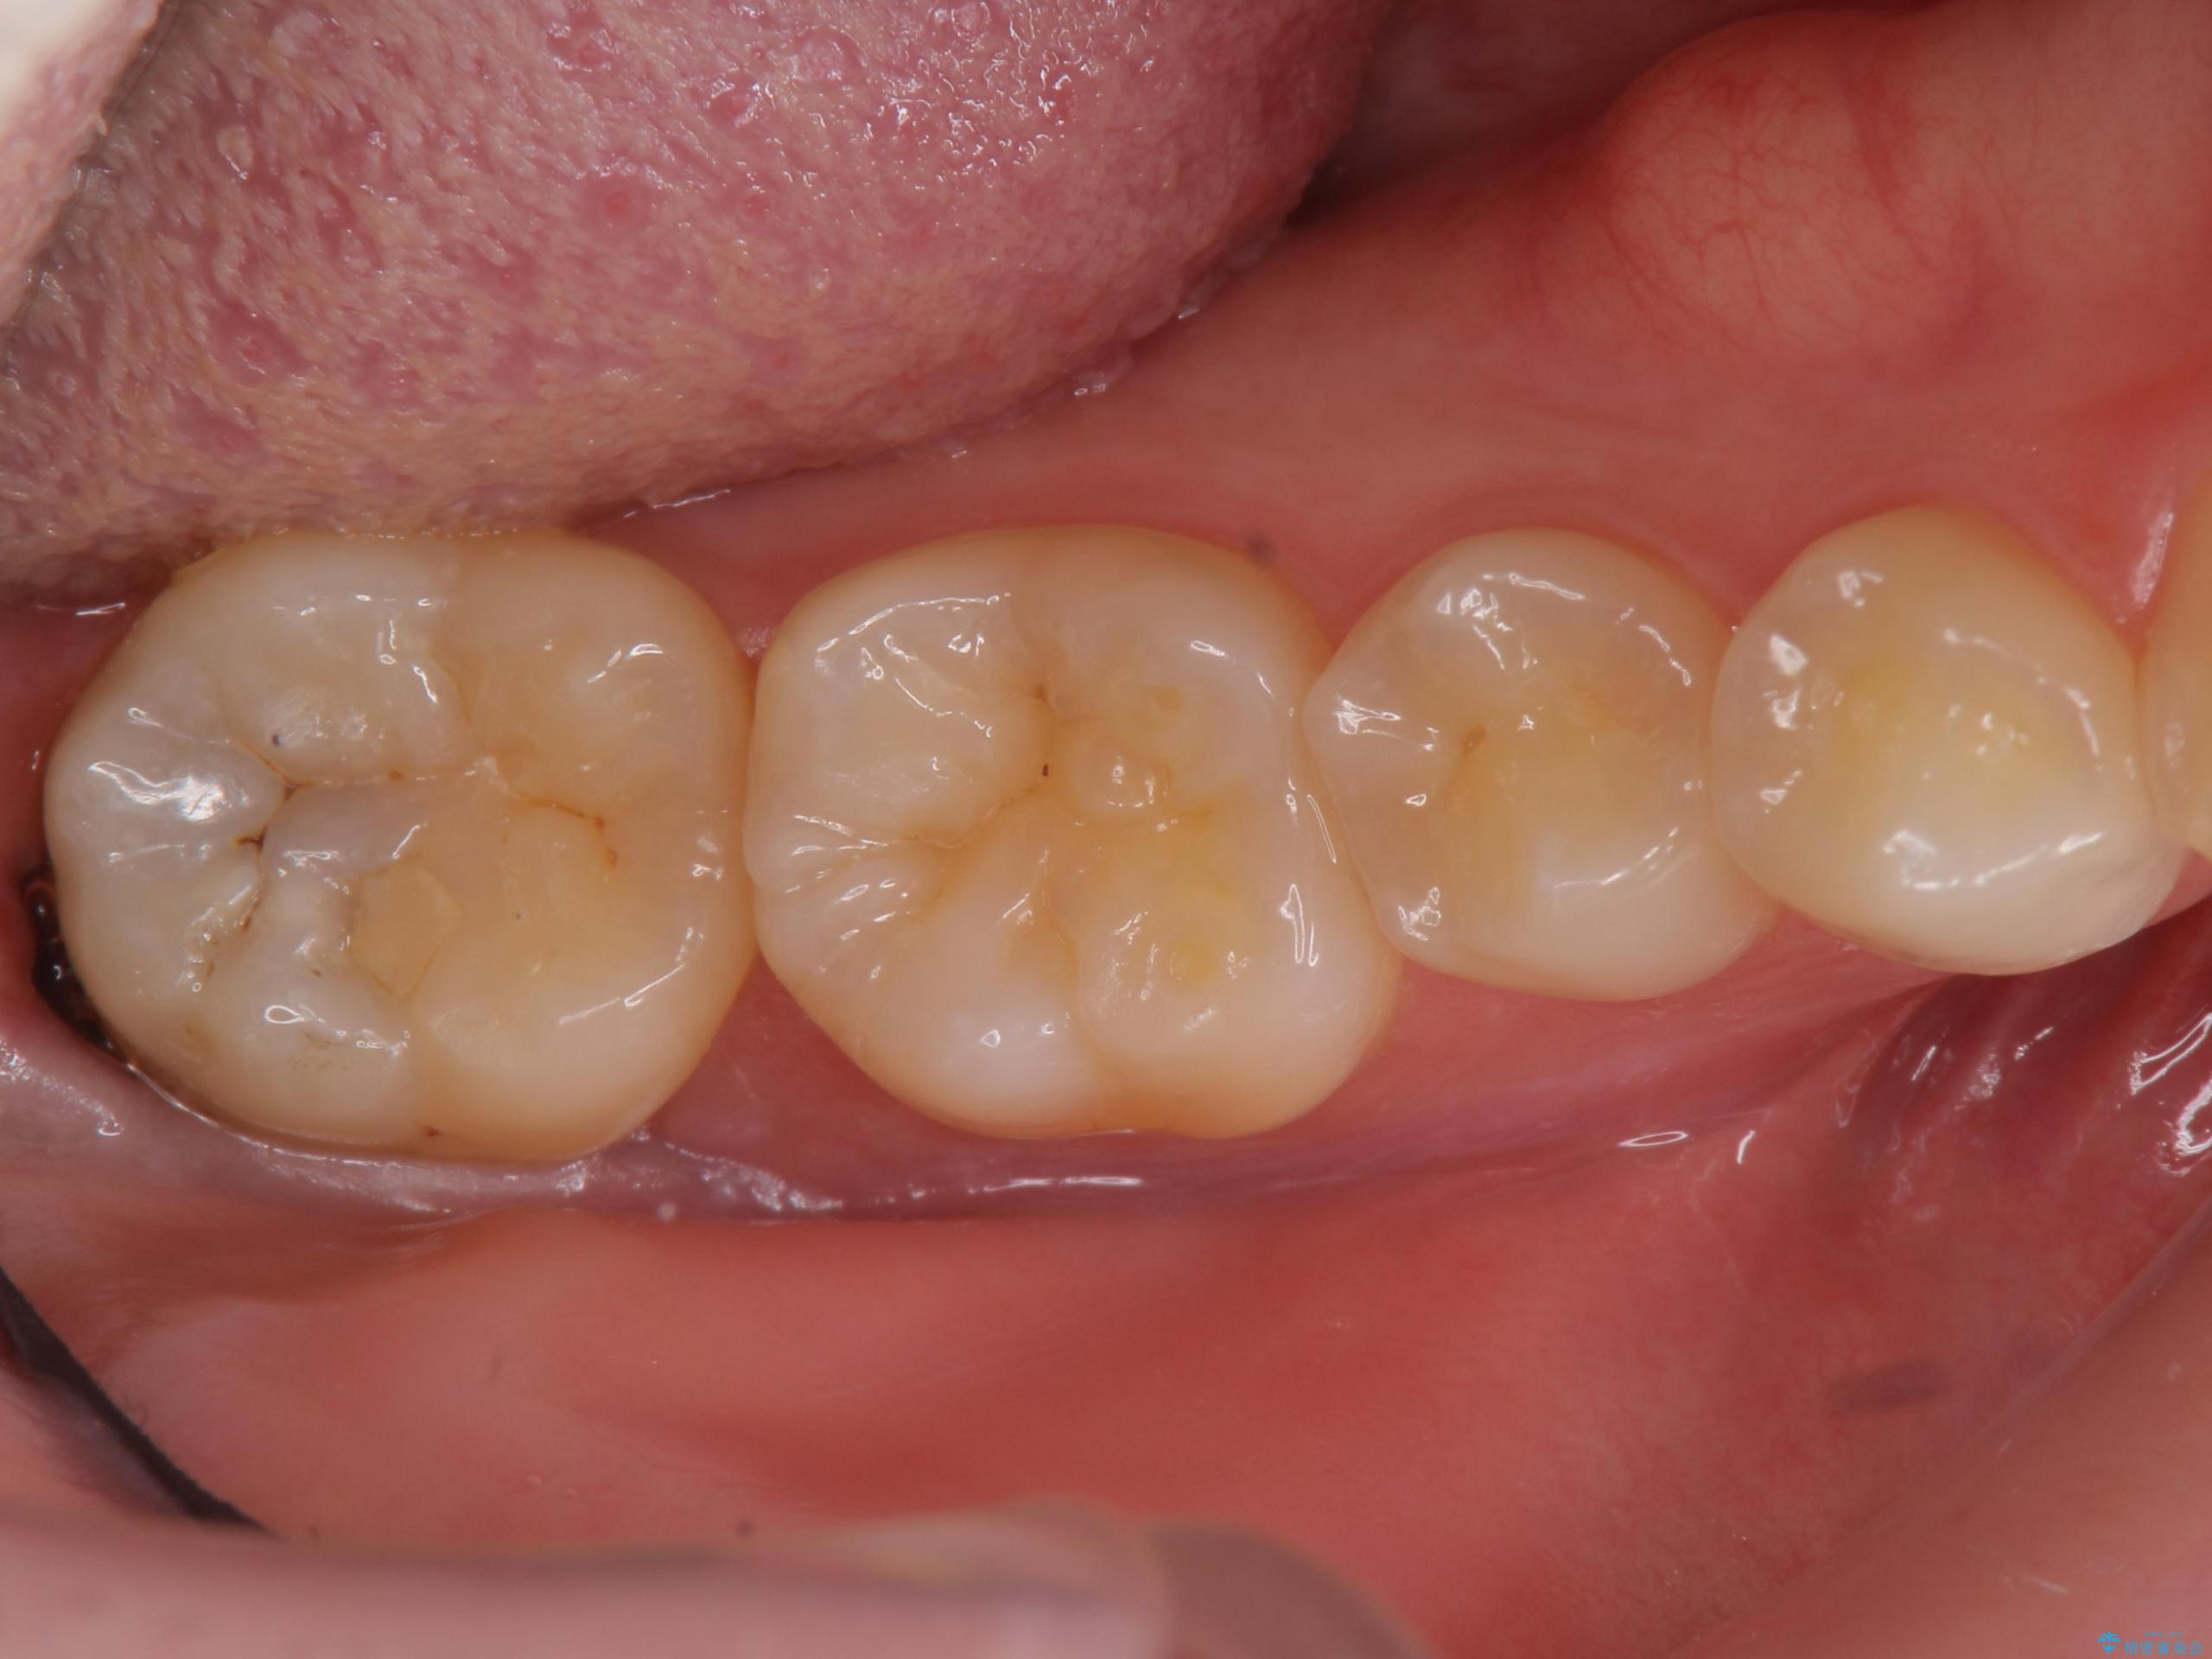

- 検査の結果虫歯が見つかった患者様です。

親知らずを抜歯してから虫歯を除去した後、ゴールドの詰め物で修復します。

比較的大きな虫歯でしたがゴールドでの修復にすることで歯の削る量を抑え、精度の高い治療を行うことができました。

親知らずの問題も同時に解決することで今後の虫歯リスクを抑えています。